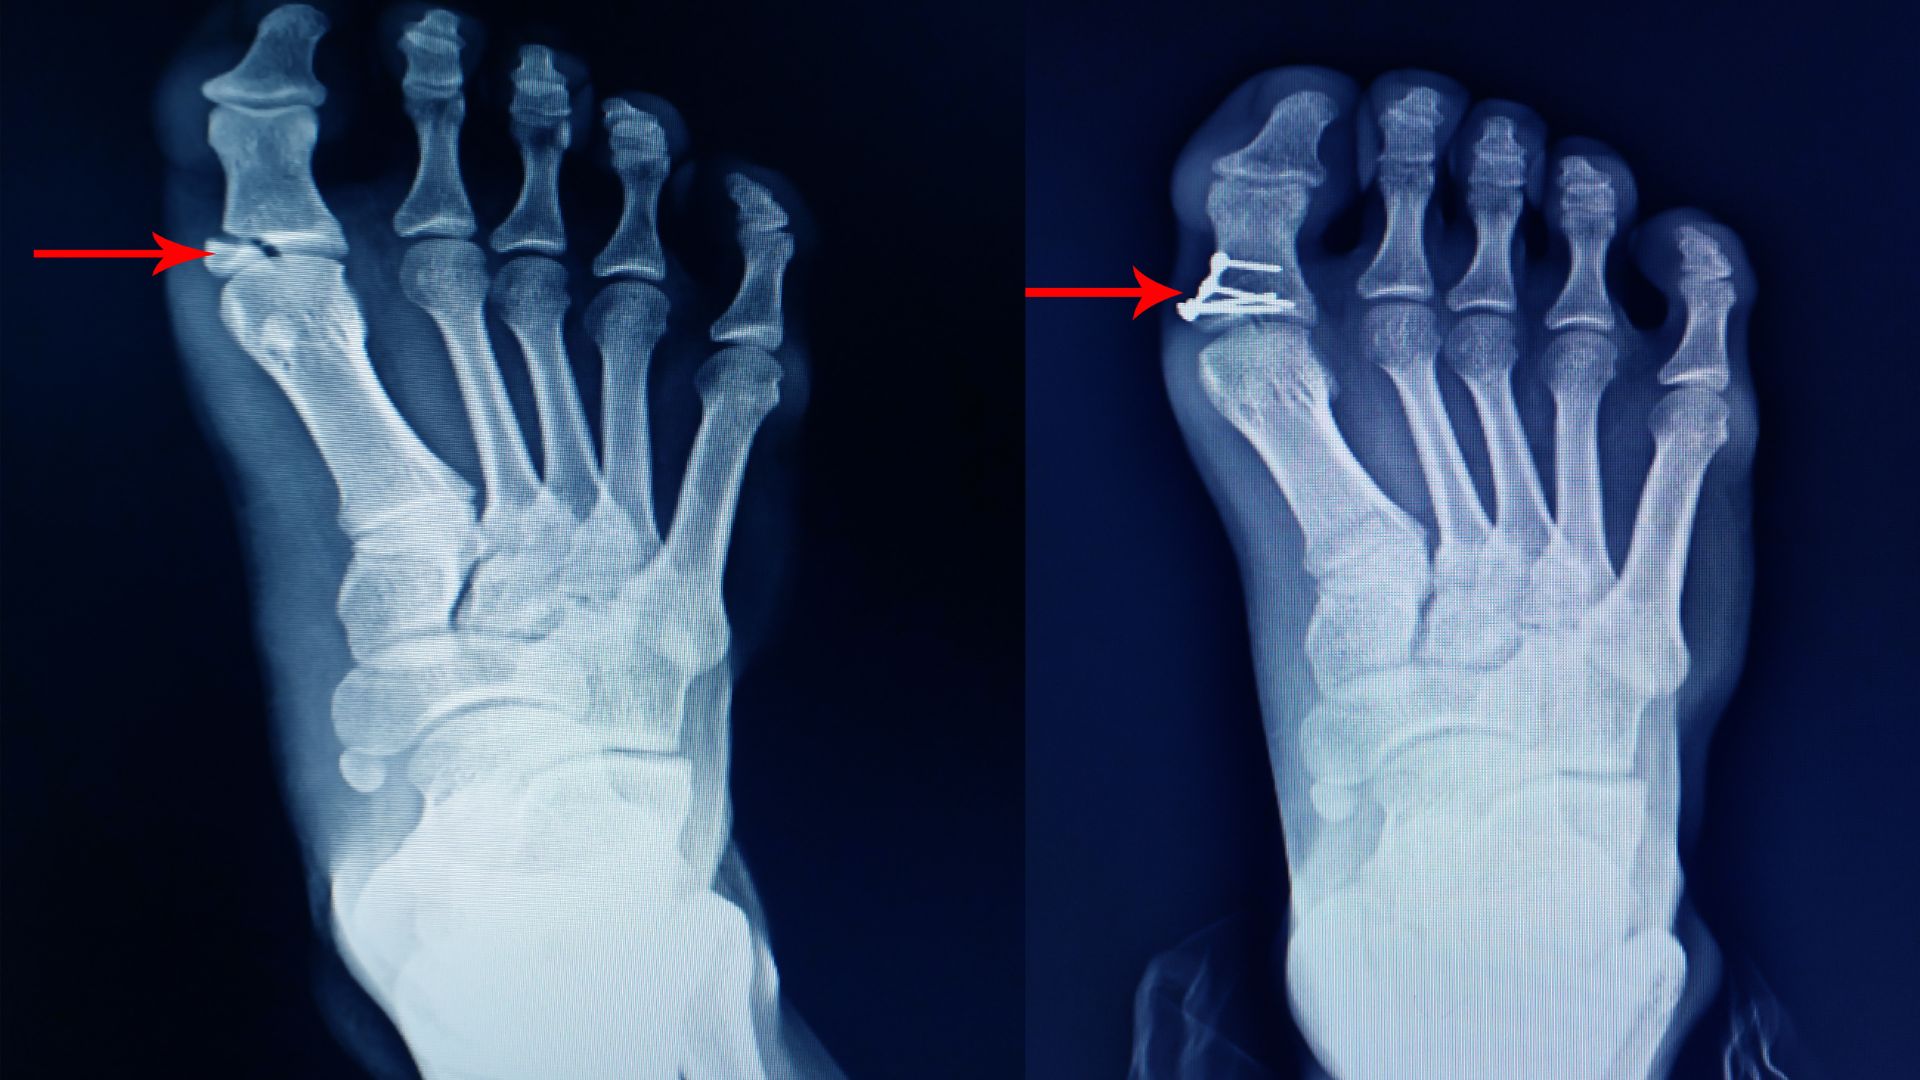

- Gãy xương bàn chân hoặc xương ngón chân, bao gồm gãy kín, gãy hở hoặc gãy do stress.

- Biến dạng bàn chân như bàn chân bẹt, hallux valgus (ngón cái vẹo ngoài, còn gọi là bunion).

- Đánh giá kết quả sau điều trị bảo tồn hoặc phẫu thuật.

- Theo dõi quá trình liền xương sau gãy.